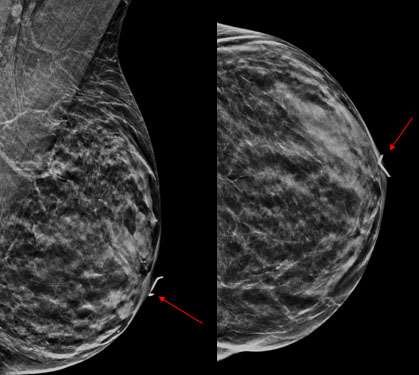

As Paget’s disease of the breast may be multicentric, it is essential to evaluate the entirety of the breast outside of the nipple/areola region to assess for additional sites of tumor. Mammogram findings of Paget’s disease of the breast include thickening of the skin at the nipple and areola, nipple retraction/inversion, microcalcifications, masses, or architectural distortion. However, a mammographic correlate may not always be seen. Ultrasound is often helpful for further evaluation when the mammogram is negative or when patients complain of a palpable lump. Ultrasound findings may include skin thickening of the nipple, heterogenous hypoechoic areas, areas of increased vascularity, discrete masses, and dilated ducts.